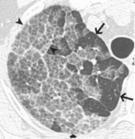

巨检显示肺脏可明显变硬,重量增加。肺实变与代偿肺气肿并存。光镜下肺泡结构基本正常,肺泡内充满细颗粒状、无结构的PAS染色阳性蛋白样物质,Ⅱ型细胞增生、肥大,胞浆内板层小体增多,板层小体成同心圆状排列。巨噬细胞数目及体积也明显增加。肺间质可有纤维化出现,有作者提到锁骨上淋巴结内可查及蛋白样物质。